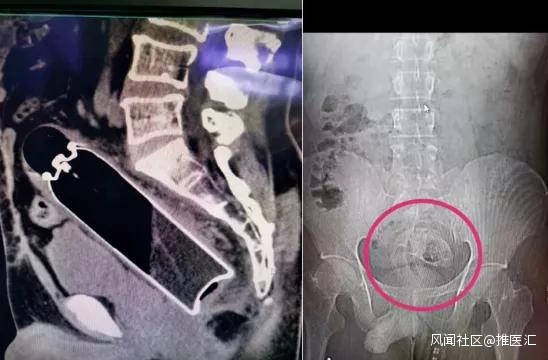

肛腸科

討厭啤酒瓶、燈泡、羅非魚、泥鰍等一切不應該出現在肛門的物品和生物……..